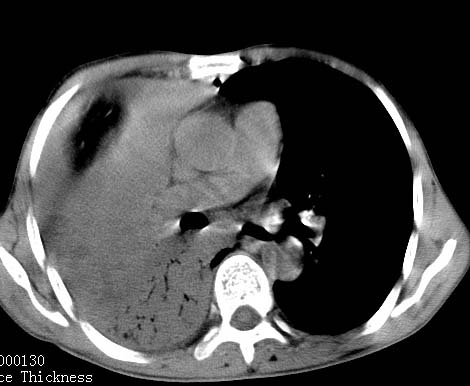

病人女 60岁 咳嗽 气促十余天,大叶性肺炎.

右肺上下叶均见 大片状密度增高影,边界清晰,其内可见支气管充气征,气管支气管通畅。纵膈略向右移位,其内无肿大淋巴结影。首先考虑炎性病变。不排除一些特异性的炎症。不知道发烧吗??wbc高吗??建议治疗后复查!!

看影响还是首先考虑炎性改变,建议实验室检查,还有要警惕炎性肺泡癌,具有的枯枝征象。

右肺感染性病变(大叶性肺炎可能);建议抗炎治疗后复查。

看影像还是首先考虑炎性改变,建议实验室检查,还有要警惕炎性肺泡癌,具有的枯枝征象